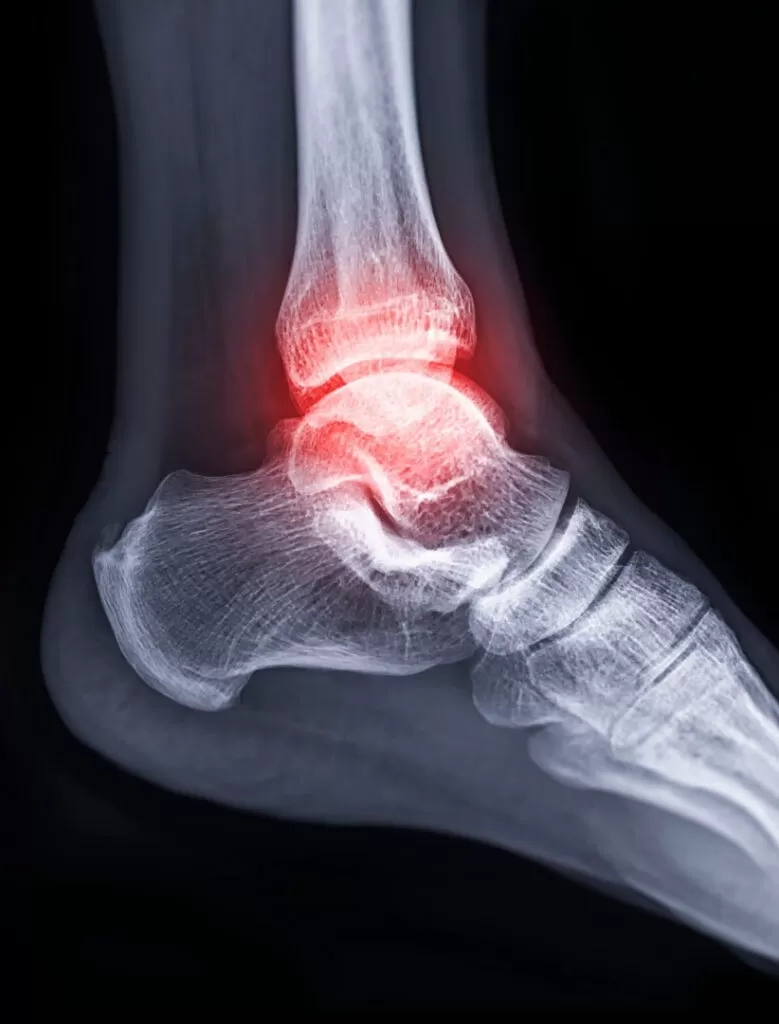

Spor Sakatlığı; sportif aktivite esnasında (antrenman ve/veya müsabaka sırasında) meydana gelen her türlü hasarın kollektif adıdır. Spor sakatlıkları sonucu ortaya çıkan sağlık problemlerinin hiç de azımsanamayacak kadar sık olduğu aşikardır.

Spor sakatlıklarında özellikle aşırı kullanıma bağlı yaralanmalar (Bkz. Aşırı kullanıma bağlı sakatlıklar), zamanında fark edilip önlem alınmaz ise kişinin uzun süre sportif aktiviteden uzak kalmasına neden olmaktadır. Tanı konulmasında geç kalınan olguların tedavileri de uzun sürmektedir. Aşırı kullanıma bağlı yaralanmaların tedavisi kadar bunlardan korunma yöntemleri de önemlidir. Yaralanmaların ortaya çıkışını kolaylaştıran faktörlerin iyi tanımlanması ve mekanizmalarının iyi bilinmesi, bu tür sakatlıkların önlenmesinde önemlidir.